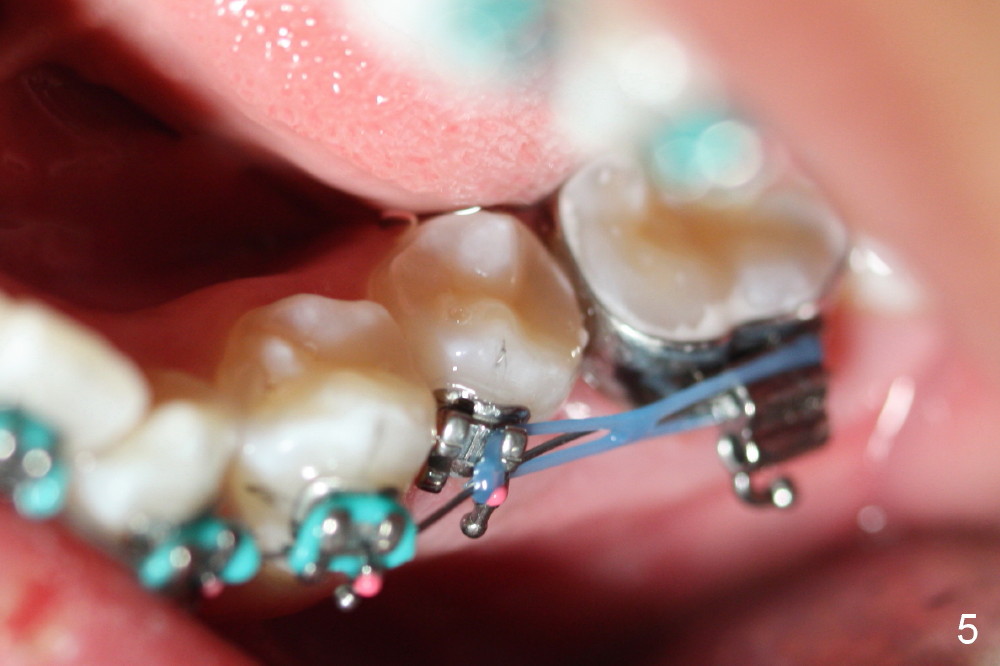

Joshua, 11 years old, has dental crowding (Fig.1), particularly in the lower arch (Fig.3) with molar Class I relationship (Fig.2). The lower 5s rotate (Fig.2 black lines), which are corrected with power chains (Fig.4,5) after bracketing and placing .012" niti wires (Fig.6).

Next visit the same wires may be kept with attention to engage the lower one to the mesial wings of L5 brackets. Note the condition of wire engagement before removing them.